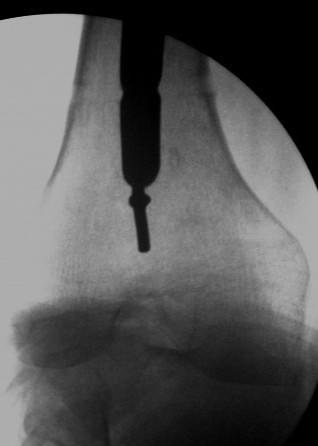

The second picture shows a plain guide wire inserted thro the nail, prograde, hammered out thro the distal femur, out thro the skin. A beaded guide wire being railroaded on the earlier G W into the distal end of the nail.

Dr Eid, you may also appreciate these.

This picture shows the beaded guide wire into the nail from its distal end.

V M Iyer